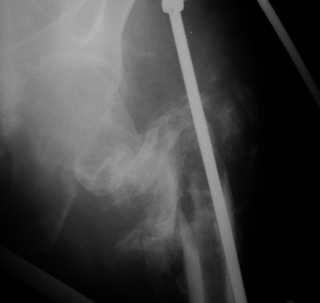

Последствия чрезвертельного перелома бедренной кости

Пациент С., 45 лет, преподаватель одного из ВУЗов г. Москвы, 3 года назад получил чрезвертельный перелом левой бедренной кости, по-поводу чего в одной московских больниц лечился методом скелетного вытяжения.

Развилось нагноение в области перелома, после чего имелся свищ по наружной поверхности бедра (рис. 1 - фистулография). Через 1 год воспалительный процесс был купирован. Свищ закрылся самостоятельно.

При осмотре: левое бедро укорочено на 10 см, нижняя конечность находится в положении наружной ротации 50 градусов, свищей нет.

Рентгенологическая картина — рис. 2. При КТ: признаков аваскулярного некроза головки бедренной кости нет, головка находится в ретроверсии (рис. 3).

1 месяц назад нами произведена остеотомия костной мозоли, наложен спице-стержневой аппарат на левые бедро и таз. На 14 сутки после операции при дистракции в аппарате отмечено нагноение послеоперационной раны. Края раны были разведены, выполнена контраппертура для ее дренирования. На данный момент воспаление купировано (рис. 4,5). В настоящий момент длина конечности восстановлена, ротация кнаружи устранена (рис. 6). На сем 1 этап лечения мы считаем законченным.

1 вариант — «Остеосинтез». Фиксация штифтом Гамма с антибактериальным покрытием (правда, шеечный винт цементом с антибиотиком покрыть не получится). Вопрос: как вывести головку бедренной кости в положение антеверсии, что бы шеечный винт при фиксации прошел через шейку и головку бедренной кости?

2 вариант — «Эндопротезирование». Иссечение костных разрастаний, удаление головки бедренной кости, установка спейсера с антибиотиком, эндопротезирование через 6-10 месяцев.